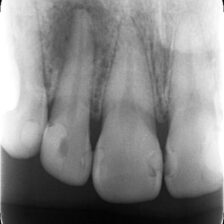

各種精密な診査、納得の治療説明

本当に根管治療が必要か?必要だとしてどの歯が原因なのか?

各種精密な診査を行い説明を行います。

また、根管治療によりどのくらいの成功率で残せるのか?

当院では世界的なエビデンスデータを用いながら当院オリジナルの治療実績も踏まえてご説明いたします。